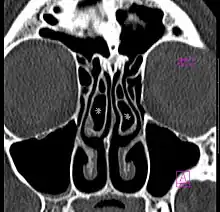

-

Large concha bullosa -